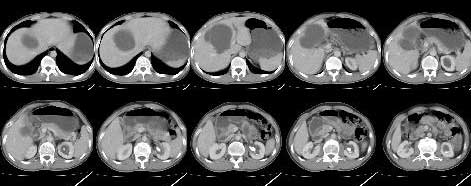

标题: CT5364:肝内囊性病变

m 42 肝内囊性病变2月,之前有多发外伤

如果病史明确,可以考虑外伤性胆汁性肝囊肿。

支持,但要排除肝单纯性囊肿

结合病史考虑外伤性胆汁性肝囊肿

(在受伤时做b超有无异常要是当时没做b超应和先天肝囊肿胆总管囊肿区别)

支持!但单纯囊肿也不能完全除外;另外右肾可见小囊肿;左肾盂示扩张,其内示密度增高影(钙化或造影剂存留,建议对比平扫),考虑左肾盂旁囊肿。

1,胆汁性肝囊肿(外伤性);

2,左肾盂旁囊肿.

不知外伤后有没有查腹部,肝脏有没有外伤性改变,如出血\\挫伤等,如果有的话可考虑为外伤后囊腔形成,至于是胆汁性肝囊肿还是其它性质的囊肿,有待进一步检查;

如果当时外伤后没有查过腹部,或者说肝脏并没有出血挫伤,那么我们所说的只能是猜测而已;

考虑肝囊肿,外伤所致假性囊肿待排。双肾囊肿